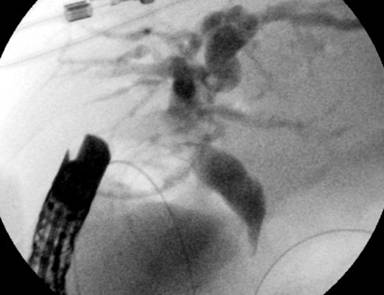

Upper endoscopy had previously shown duodenal stenosis due to circumferential ulcerated and infiltrative lesions in all cases. Facing a high probability of an unsuccessful ERCP, we discussed the possibility of endosonography-guided biliary drainage and duodenal stenting with the surgical and oncological teams. We performed the procedure following the same sequence in all cases. For the whole procedure, the patient was under general anesthesia and fluoroscopic guidance was used. A therapeutic duodenoscope (TJF-160, Olympus, Tokyo, Japan) was introduced and advanced until the duodenal bulb. A 0.035 guidewire (Jagwire®, Boston Scientific, Natick, MA, USA) was advanced through the duodenal stenosis until the proximal jejunum (Figure 1). The stenosis was dilated with a dilation balloon (CRETM Balloon Dilator, Boston Scientific, Natick, MA, USA) until 15 mm. The duodenoscope was advanced but the major ampulla could not be identified. The guidewire was left in place and the duodenoscope was removed. A linear array echoendoscope (GF UCT-140, Olympus, Tokyo, Japan; Alfa 5 processor, Aloka, Tokyo, Japan) was introduced. Endosonography examination was performed to look for the dilated common bile duct, the largest left intrahepatic duct and the presence of collateral veins. In all cases, the largest left intrahepatic ducts were smaller than 6 mm and we did not attempt the antegrade transhepatic access. The common bile duct was punctured with a 19-gauge needle (EUSN-19T, Cook Medical, Bloomington, IN, USA) (Figure 2). Bile was aspirated and contrast was injected to confirm an adequate position of the needle (Figure 3). After confirmation with fluoroscopy, a 0.035 guidewire (Jagwire®, Boston Scientific, Natick, MA, USA) was advanced through the needle into the common bile duct and the needle was retrieved. A 6-Fr cystotome (Endo Flex, Voerde, Germany) was then inserted over the guidewire to create a bilioenteric communication (Figure 4). In four patients, a partially covered biliary self-expandable metallic stent (WallFlex® 60/100 mm, Boston Scientific, Natick, MA, USA) was inserted into the common bile duct and successfully deployed, creating a choledochoduodenal fistula (Figure 5). In one patient (Patient#2), we deployed an uncovered biliary metallic stent (WallFlex® 60/100 mm, Boston Scientific, Natick, MA, USA). The echoendoscope was removed and the duodenoscope was introduced over the duodenal guidewire. A non-covered duodenal self-expandable metallic stent (WallFlex® 120/220 mm, Boston Scientific, Natick, MA, USA) was inserted over the guidewire and deployed in all patients (Figures 6 and 7).

Figure 3. Contrast injection. |